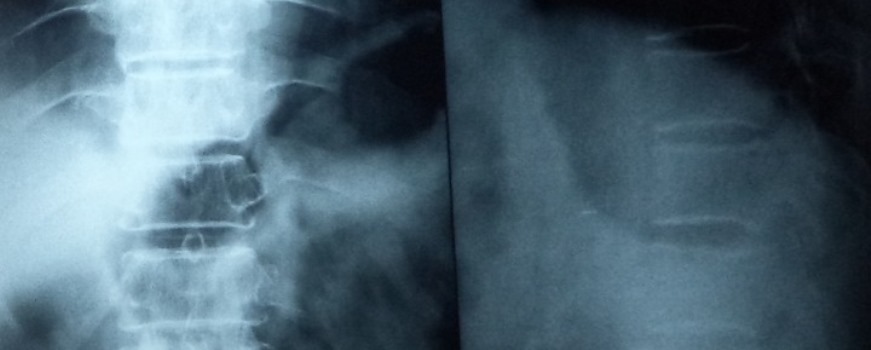

These fractures can be treated very well with the help of Pedicular screw system. This system and the C arm image intensifier equipment are very useful to correct and fix these vertebral fractures in the best possible position. After the spinal fixation, it is possible for the patients to sit and walk very early and the fixation gives very good pain relief.

Some patients will get disc prolapse in cervical as well as lumbar regions. These intervertebral discs are soft shock absorbing materials in between the vertebra. Due to any acute strain, sports activities, weight lifting activities or during accidents these discs get injured and they prolapse or protrude into the vertebral canal.

This prolapsed disc will start compressing the spinal cord or nerve roots. So, this cord compression or root compression will cause neurological problems as well as intractable pain. To diagnose a disc prolapse we need to get an MRI of the affected region. If the disc prolapse symptoms are not relieved by conservative management then surgery maybe indicated. There are many types of discectomy or disc removal procedures available. Open techniques are time-tested and useful.